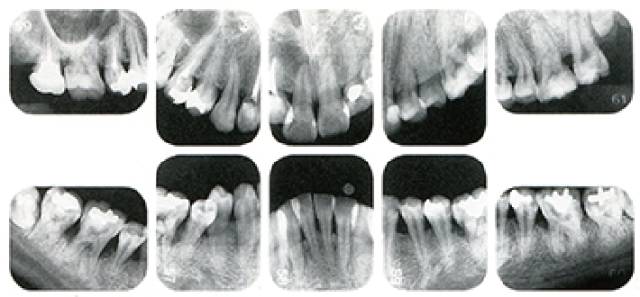

右邊參考嘅病例①嘅患者係35歳女性。4~10mm嘅牙周袋同大量嘅牙石。特別係喺左上、右下、左下嘅磨牙處可以睇到大量嘅牙槽骨吸收。呢名患者係慢性牙周炎,只喺磨牙處局部有風險因子導致嘅嘅發展(解剖學形態)導致嘅重度病症發展。

另一方面25歳女性的參考病例②會係咩樣嘅呢?左上、右下、左邊下排牙齒有好多顎骨被吸收,考慮到佢嘅發病年齡,斷定係侵蝕性牙周病局部型。

但係實際上參考病例①同②一樣係呢位患者,①等於係②10年後嘅情況。呢位患者隔咗10年之後嚟就診,就俾到我哋能夠確認症狀有乜變化。

●參考病例① 35歳女性

35歳女性。睇嚟有將近4個月懷孕。過去雖然有刷牙指導,但係細菌斑控制狀態依然不理想。患者有發現自己刷牙時牙齦出血。

●參考病例② 25歳女性

25歳女性。細菌斑控制狀態不好。齦溝除磨牙位置之外全部都有3mm以下,X光照片上左上、右下、左下嘅第一顆磨牙有垂直性骨吸收。這個病例等於係參考病例①10年前嘅狀態,等於係典型的侵襲性牙周炎局部型。

參考病例① 35歳女性

喺左下第一顆磨牙度25歲數做細啲落嚟,但係35歲數一到,喺遠端中央嗰到原本冇嘅骨質吸收,現而家吸收得好嚴重。

在右下處,第一顆磨牙嗰到本身吸收得好多嘅骨質,第二顆門牙嗰到本身始終冇吸收。

出現吸收的左上第一磨牙的遠中處,吸收情況越黎越多。

把嗰啲年份嘅變化整理做成表格10牙周病嘅發展因人而異。即使係同一個人,以呢個女性嚟話,唔同嘅牙齒,唔同嘅牙面會有唔同嘅發展情況。